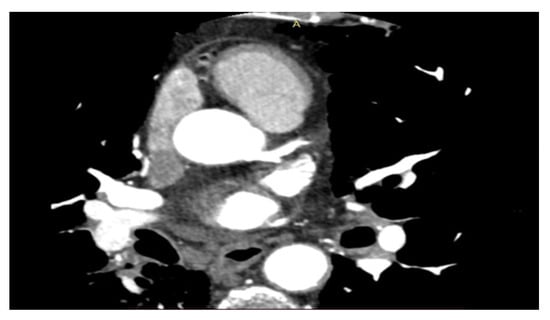

In this protocol, researchers will investigate the potential adverse effects of chest radiotherapy on the heart using the CT scan and MRI (Figure 1 and Figure 2). They will evaluate the coronary vessels and myocardial tissue to determine if and under what circumstances radiation caused heart damage. This information could then be used to develop new follow-up schedules and strategies to ensure that patients are effectively monitored for cardiotoxicity. Other authors have also been investigating the cardiotoxicity of RT using different techniques and protocols. However, the use of MRI is recognized as having its disadvantages, including high cost, long image-acquisition time, and limited availability. Until these challenges can be addressed, its use in cardio-oncologic populations will likely remain limited to those in whom echocardiographic assessments are of poor quality or inconclusive [45,46,47,48,49,50,51,52,53,54].

Figure 1. Coronary CT scan.

CT anatomic imaging is advantageous for detecting non-obstructive coronary artery disease CAD early in the disease process before ischemia develops, allowing for the earlier use of preventive medications. Coronary computed tomographic angiography (CCTA) can noninvasively detect and quantify non-calcified plaque and coronary stenosis and has a powerful negative predictive value when ruling out CAD, with lower radiation exposure than other modalities. On the other hand, coronary artery calcification (CAC) scans are able to evaluate calcified plaque and have even lower radiation exposure. CAC scans can identify coronary atherosclerosis in patients with cancer before RT treatment and might predict cardiovascular outcomes. Cardio CT is important for the study of cardiotoxicity and can be combined with clinical data using machine learning models for individualized risk prediction [34,35,36,37,38].